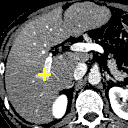

Figure 7: Example comparison among ADDD + inv (c/d), ADDD (e/f), ADD (g/h), AD (i/j) and D (k/l) networks.

In Figure 7, we compare ADDD + inv, ADDD, ADD, AD and D. It shows that network cascading better aligns the images with the presence of large displacement, while the invertibility loss has a remarkable effect on the liver boundary.